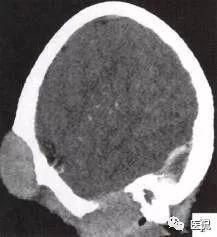

颅脑CT示:图A〜D,CT平扫示左侧额骨、蝶骨见溶骨性骨质缺损,边界清晰,周围无硬化边,伴有软组织肿块向脑外生长,边缘光滑,脑内无明显侵犯;

图E、F,横、 矢状位CT增强示软组织肿块轻度均匀强化,两病灶间亦见强化软组织影;

图G,矢状位骨窗示骨质破坏,边缘光整,无硬化边;